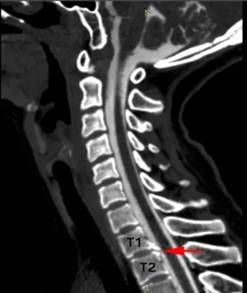

小江的脊柱磁共振检查可见第1、2胸椎之间有“骨刺”形成(红箭头)刺破硬脊髓膜,造成脑脊液外漏(蓝箭头)医院供图